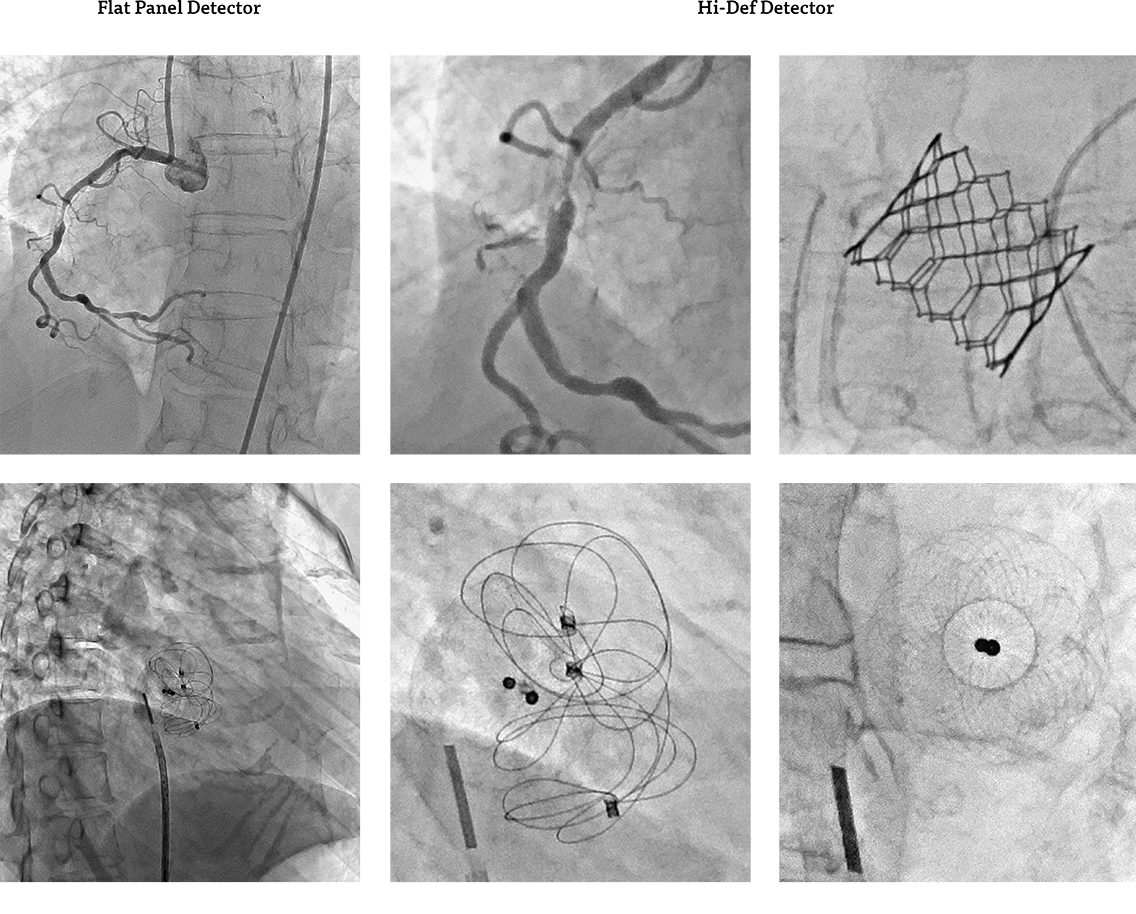

Здатність збільшувати поле зору при одночасному збільшенні внутрішньої просторової роздільної здатності за допомогою технології Hi-Def покращує візуалізацію під час критичних аспектів ендоваскулярних втручань.

Цей унікальний гібридний FPD 30 x 30 см або 30 x 40 см поєднує в собі технологію зображення високої чіткості на основі CMOS, що підвищує просторову роздільну здатність до 6,6 пар ліній на міліметр (lp/mm) із розміром пікселя у 76 мікрон     (рис. 1).

Ця унікальна технологія пропонує стандартні режими збільшення 40 см, 30 см, 25 см, 20 см, 15 см або 10 см (FOV) і три додаткових режими Hi-Def з 7 см, 5 см і 3 см FOV, дозволяючи візуалізувати найдрібніші. У будь-який момент часу доступні обидва режими, і за потреби вибір між двома режимами можна швидко змінити, без додаткової затримки процедури.

Рис. 1 Hi-Def детектор забезпечує максимальну ефективність і забезпечує більш ніж у 2 рази вищу просторову роздільну здатність у порівнянні з режимом FPD із розміром пікселя у 194 мікрон (ліворуч) та режиму високої роздільної здатності з розміром пікселя у 76 мікрон Hi-Def (праворуч). Завдяки більшим розмірам пікселів у звичайному режимі можна візуалізувати лише до 2,6 пар ліній/мм без будь-яких накладень або втрати зображенням інформативності.

Вимоги до зображення високої чіткості в режимі реального часу постійно ростуть із розвитком мінімально інвазивних методів лікування судинних патологій, таких як інсульт чи аневризми. Вищі режими просторової роздільної здатності детектора Hi-Def можуть забезпечити чіткіші та візуально кращі зображення, кількісно визначені за допомогою стандартних фізичних показників, порівняно з традиційними зображеннями FPD.1

Наприклад, функції передачі модуляції (MTF) нового детектора у Hi-Def і режимі демонструють здатність відображати структури, які інакше були б накладені (тобто не візуалізовані) у звичайних режимах роботи FPD. Неминуче Hi-Def перевершує звичайні FPD у просторовій роздільній здатності.3

Під час інтервенцій, використовуючи режими FPD зі стандартною роздільною здатністю для грубої навігації, катетери та пристрої направляються від місця доступу до проксимального місця ураження. Остаточне розміщення та розгортання пристроїв виконується у режимах високої роздільної здатності Hi-Def із меншими FOV. У сліпому дослідженні, яке порівнювало зображення Hi-Def і FPD, зображення Hi-Def були оцінені як чіткіші та візуально кращі [оцінка «набагато кращі» в 73% випадків] порівняно з зображеннями з нижчою роздільною здатністю FPD.2